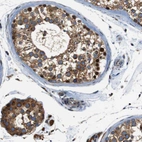

Immunohistochemical staining of human liver shows moderate cytoplasmic positivity in hepatocytes.